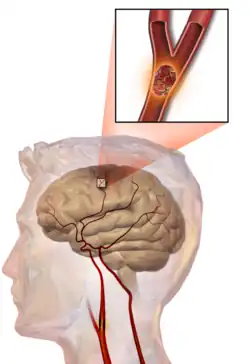

One of the top causes of death worldwide, strokes are disruptions of the blood supply to the brain. These disruptions can be triggered by a variety of ways, the most common of which are the rupturing of an artery (or hemorrhage), or blockages, which may either by from clots or other obstructions. Whatever the immediate cause, obstruction of the vascular system delivering blood to the brain can quickly lead to the death of cells in the affected areas. Like traumatic brain injury, the exact symptoms and consequences of a stroke depends on the region most affected, however there are some common characteristics. Paralysis or weakness on one side of the body- usually manifested in slurring of speech or drooping of the face- is very common since usually the blocked artery will be responsible for delivering blood to one specific brain hemisphere.